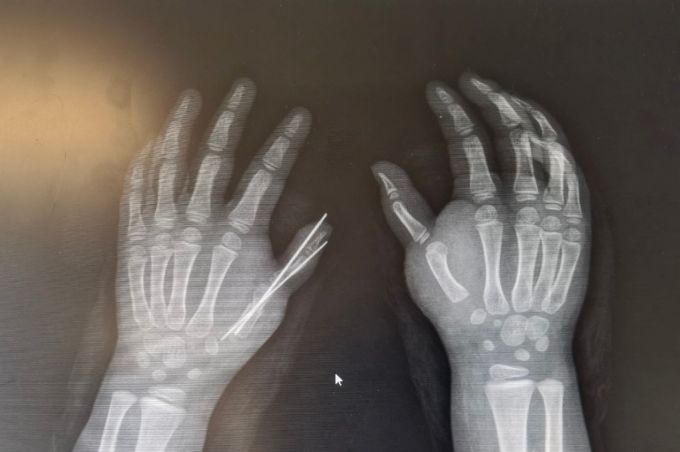

乐乐自幼被诊断为双侧拇指多指,且是先天性心脏病术后的康复者。随着年龄增长,她面临第六型掌骨遗传性畸形的问题,畸形拇指的存在严重阻碍了手指的正常发育,表现为掌骨生长异常,其两根掌骨中一根具备骨骺,另一根则不幸缺失。为解决这一复杂情况,骨科杜东鹏主任组织团队深入讨论,凭借过去做过很多类似手术,他认为要充分考虑皮瓣设计、关节矫形、肌腱转位、关节内固定、关节囊修复,以及避免损伤指固有动静脉和神经等多种因素,手术既要确保健康发育,又要进行美学重建保持美观,同时还要保障掌骨、指骨及骨骺的完整性。

在切除畸形拇指后,团队对保留下来的拇指进行了精细的掌指关节囊修复和拇短展肌重建,以恢复拇指的外展能力。同时,他们紧缩关节囊以矫正拇指的偏斜,并使用克氏针固定关节,确保拇指外形的稳定。此外,团队对拇指的皮肤进行了巧妙的修剪,实现了优美的皮瓣成形,进一步改善了术后效果。